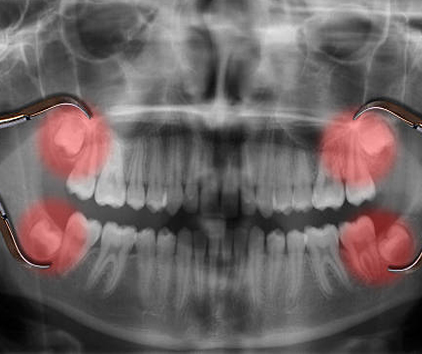

• A thorough examination, including X-rays, to assess the position and condition of your wisdom teeth.

1. Impaction: When there’s not enough space in the jaw, wisdom teeth may become impacted, meaning they are unable to break through the gum line properly.